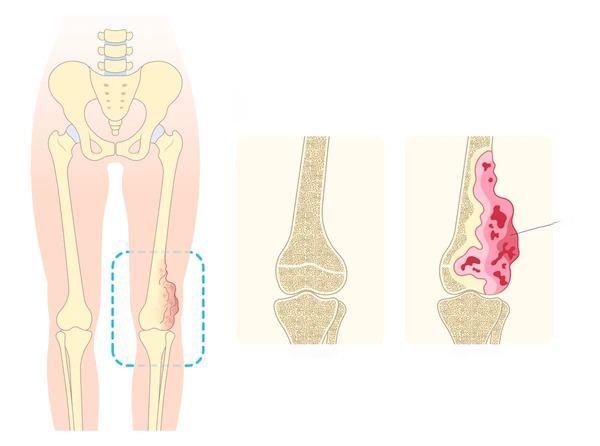

1. Osteosarcoma

- Description: The most common malignant bone tumor in children, often found in the long bones, such as the arms and legs.

3. Chondroblastoma

- Description: A rare benign tumor that typically occurs at the ends of long bones near the joints.

4. Osteochondroma

- Description: A benign tumor that forms a bony outgrowth on the surface of a bone.